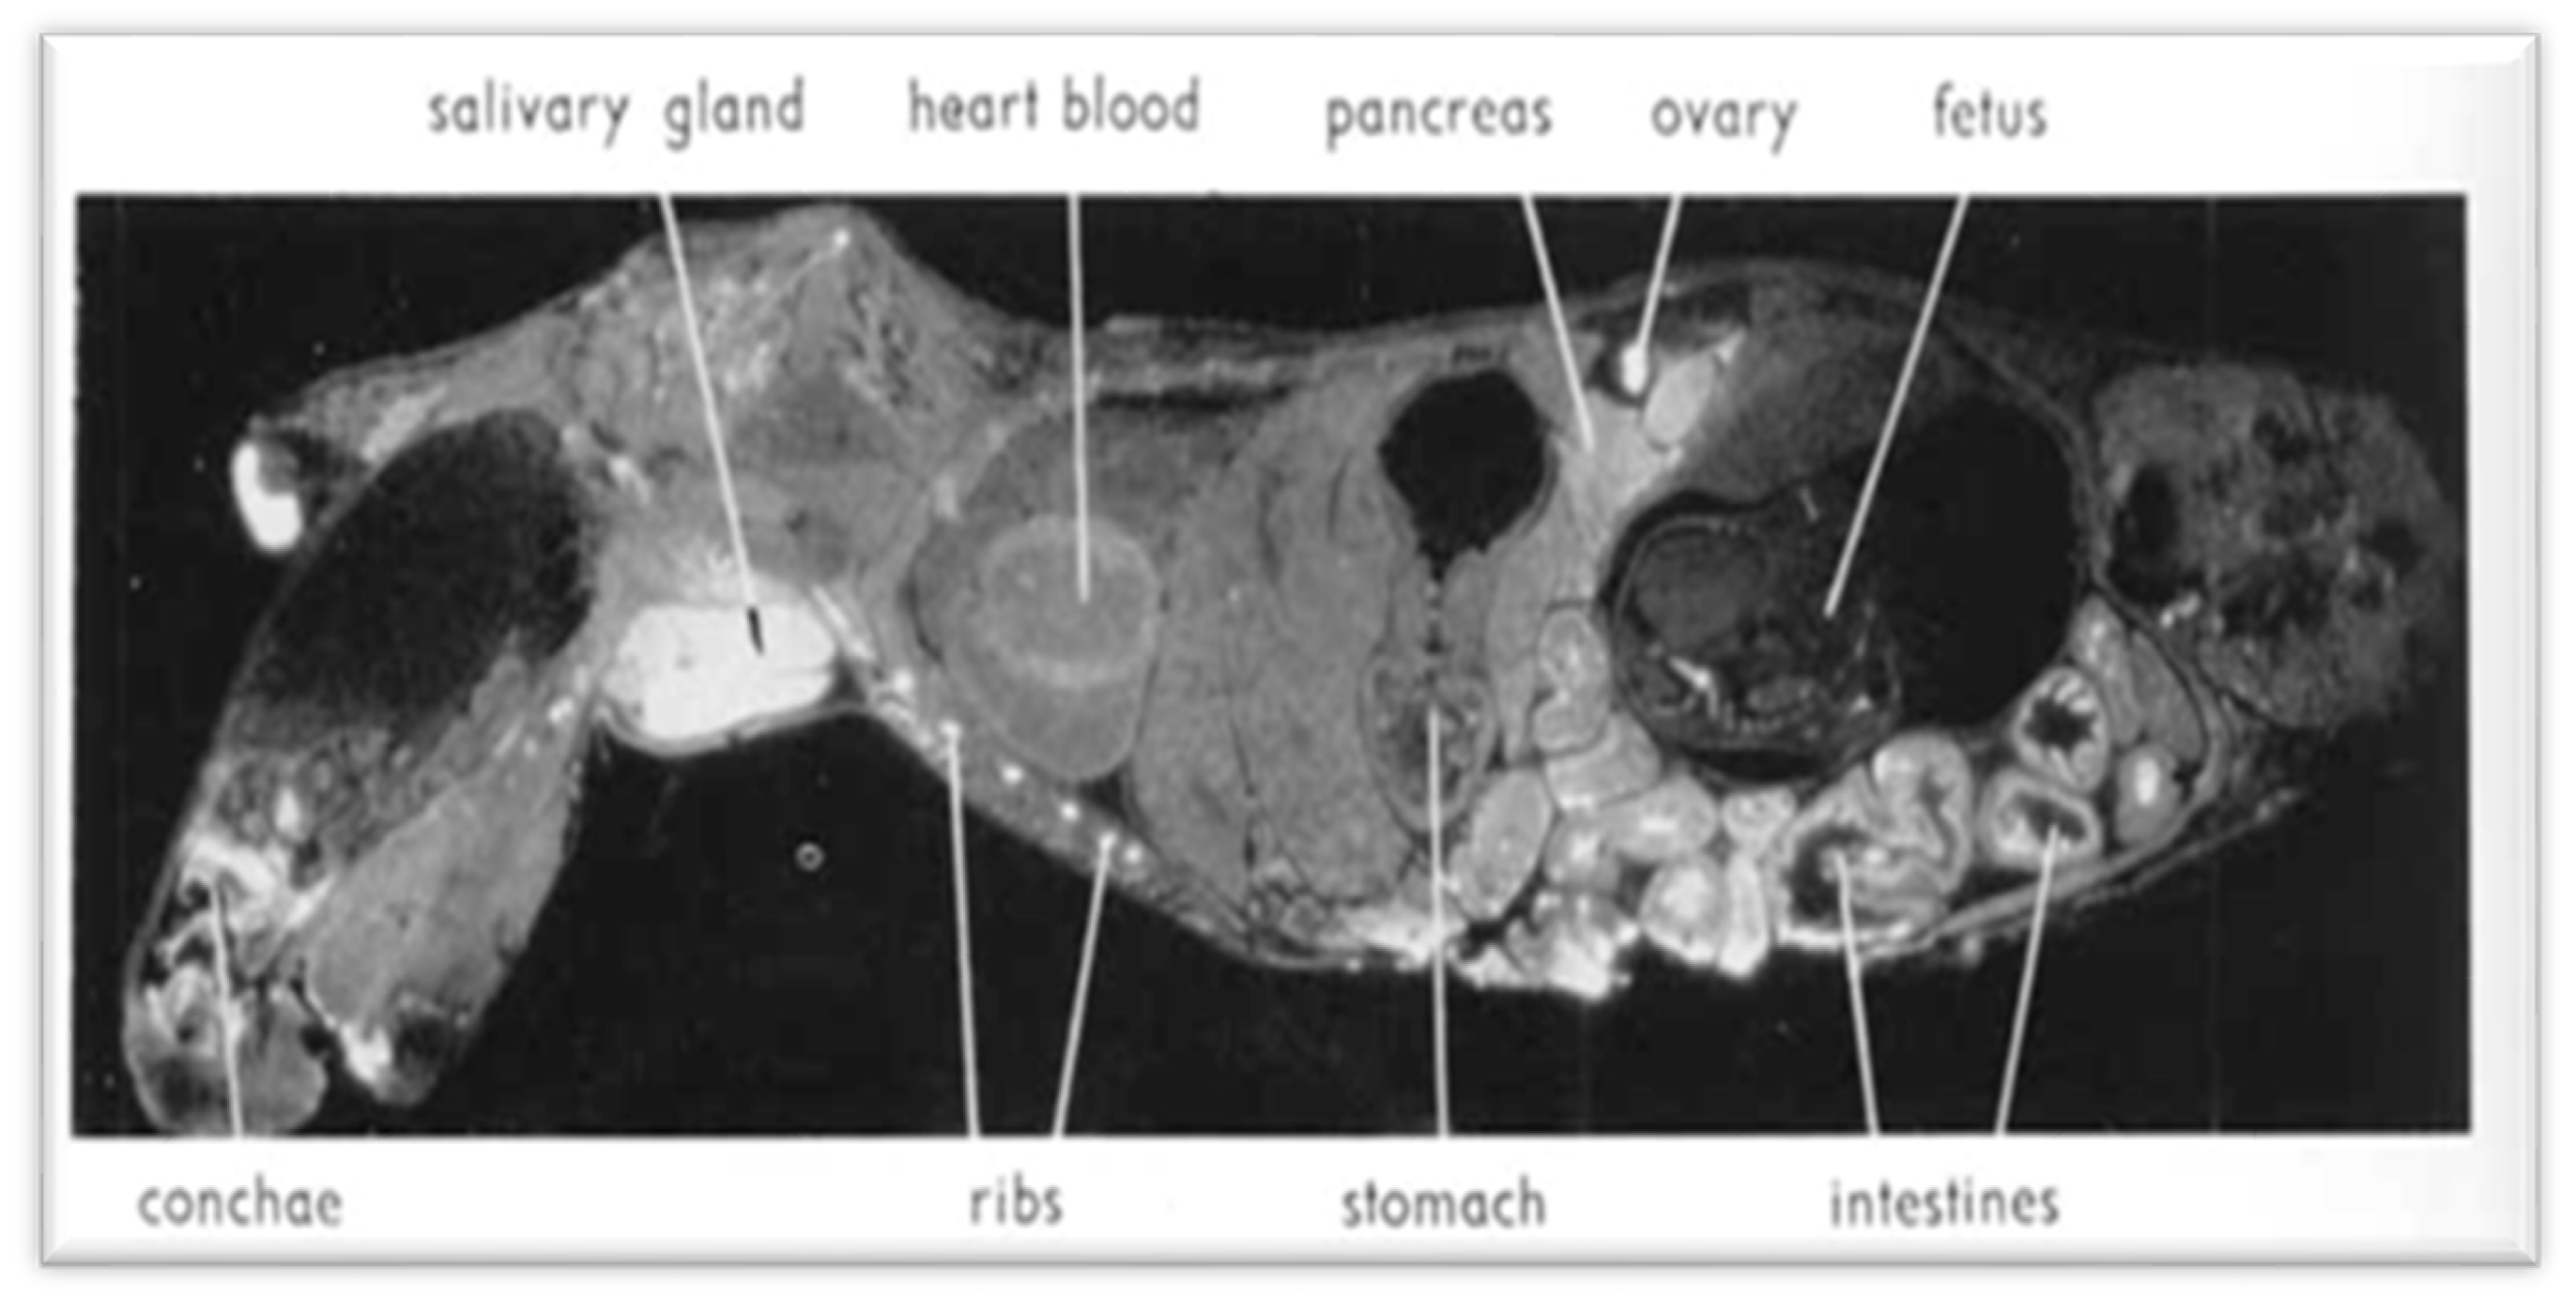

3.2. Cesium Metabolism

- Nelson, A.; Ullberg, S.; Kristoffersson, H.; Ronnback, C. Distribution of radiocesium in mice. Acta Radiol. 1961, 55, 374–384. [Google Scholar] [CrossRef]

- Ullberg, S.; Ewaldsson, B. Distribution of radio-iodine studied by whole-body autoradiography. Acta Radiol. Ther. Physics. Biol. 1964, 2, 24–32. [Google Scholar] [CrossRef]